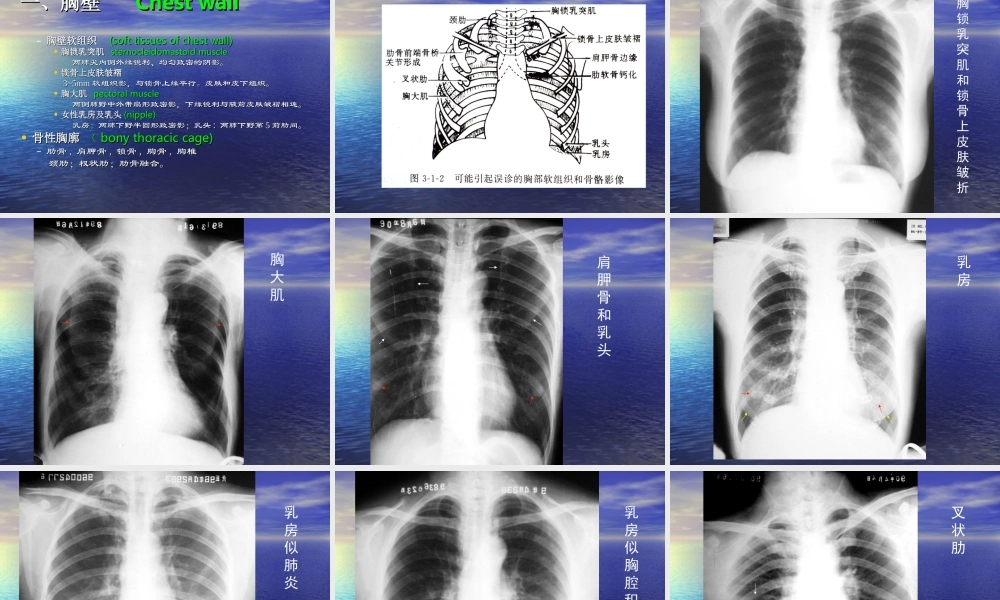

胸部普通胸部普通XX线影像诊断线影像诊断学学DiagnosticimageologyofchestdiseasesDiagnosticimageologyofchestdiseases第一章呼第一章呼吸系统吸系统RespiratorysysteRespiratorysystemm特点:特点:含有空气,良好自然对比;含有空气,良好自然对比;病变密度增加或降低;病变密度增加或降低;能直接显示病变部位、范围和性质;能直接显示病变部位、范围和性质;方法简单、应用广泛;方法简单、应用广泛;随访:随访:<<3mm3mm孤立病灶;大叶性肺炎早期以及病灶孤立病灶;大叶性肺炎早期以及病灶被遮盖被遮盖,,检查受限。检查受限。第一节第一节XX线检查技术线检查技术TechniquesofX-rayTechniquesofX-ray常规常规XX线技术;线技术;胸部胸部CTCT技术;技术;胸部胸部MRIMRI技术;技术;胸部超声技术。胸部超声技术。一、普通检查一、普通检查ConventionalexaminationConventionalexamination((一一))胸部透视胸部透视(chestfluoroscopy)(chestfluoroscopy)((二)二)胸部摄影胸部摄影::(chestradiography)(chestradiography)–后前位后前位,,前后位前后位((一般应用于床头摄影一般应用于床头摄影),),侧位侧位–前弓位:肺尖部、锁肋骨重叠病及中叶病变前弓位:肺尖部、锁肋骨重叠病及中叶病变–侧卧水平方向后前位:少量积液、肺下积液侧卧水平方向后前位:少量积液、肺下积液透视时,荧光屏上的影像以黑色表示高密度物质;以白色透亮表示低密度物质(三)、(三)、数字化数字化XX线摄影线摄影包括包括CRCR和和DR,DR,优点:优点:图像清晰度提高;图像清晰度提高;XX线的接受剂量降低;线的接受剂量降低;影像存储传输(影像存储传输(PACS)PACS)及远程医疗服务;及远程医疗服务;图像后处理,图片校正及减少重拍率。图像后处理,图片校正及减少重拍率。CRCR(computedradiography,CR)(computedradiography,CR)摄像板摄像板(IP)(IP)代替代替XX线胶片。线胶片。XX线影像线影像→→读取装置读取装置→→数字信号数字信号→→后处理后处理→→数字信号数字信号→→光信号光信号→→激光照相机激光照相机→→CRCR像片。像片。高曝光宽容度,低辐射及可调节显示窗高曝光宽容度,低辐射及可调节显示窗。。DRDR(digitalradiography,DR)(digitalradiography,DR)专用计算机直接读取感应介质记录到的专用计算机直接读取感应介质记录到的XX线影像信息线影像信息→→数字化图像重放和记录。数字化图像重放和记录。资料快速、准确光速传输,可行...